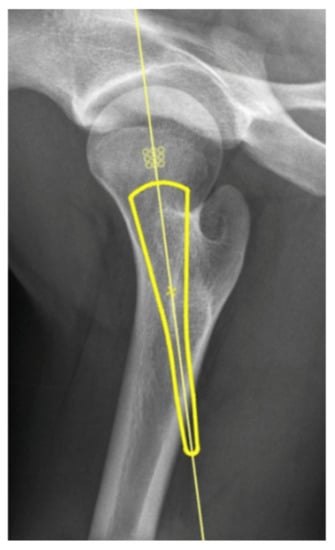

The Rate of Correctly Planned Size of Digital Templating in Two Planes—A Comparative Study of a Short-Stem Total Hip Implant with Primary Metaphyseal Fixation and a Conventional Stem

2. Materials and Methods